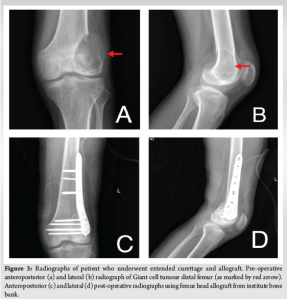

The average age of the patients in the study was 35.69 ± 12.75 years (range: 18–69 years). There were 18 men and 13 women. The distal femur were 12 and proximal tibia were 19 involved in our study. 29 patients had a primary GCT while 2 patients had a recurrent GCT. The tumors were staged radiologically using the Campanacci grading. There were eleven cases of Grade II tumor and twenty cases of Grade III tumor. Five patients had pathological fracture at presentation. In our study, 6 underwent the sandwich procedure using PMMA as a void filler (Fig. 1), 10 underwent extended curettage and autologous bone graft (Fig. 2), 11 underwent extended curettage and morselized allograft (Fig. 3), and 4 patients underwent endoprosthesis (Fig. 4).

The aim of this study was to evaluate the clinical and radiological outcomes in patients with GCTs around the knee who underwent surgical treatment, with a minimum follow-up period of 1 year. GCT is a benign primary bone tumor that is locally aggressive but has the potential for malignant metastasis [3-7]. It accounts for 5–7% of all primary bone tumors and approximately 20% of benign bone tumors [8]. Typically, GCTs occur in the epiphyseal-metaphyseal regions of long bones and predominantly affect individuals aged 20–40 years. Our study included 31 patients with GCTs around the knee. Of these, 19 patients (61%) had tumors in the proximal tibia, while 12 patients (39%) had tumors in the distal femur. A significant proportion, 20 patients (64.5%), fell within the 20–40 age group. As per to literature, it has shown more female preponderance than male [9]. Our study had involved 18 males (58%) making it greater than females in the study period, but it was statistically not significant. GCT can present with a vast variety of symptoms, for example, pain, swelling, decreased joint mobility, fracture of involved bone, neurovascular involvement of the limb, or accidental finding while routine check-up. Most of the patients enrolled in our study presented with above above-listed complaints but 5 (16.12%) of 31 patients presented with pathological fracture around knee. Evaluation for GCT involves non-invasive and invasive modalities. Initial radiographs and MRI are usually performed where it appears as a pure lytic cystic lesion that frequently, though not always, grows eccentrically in the epiphysio-metaphyseal area of the bone. The bone’s afflicted region may enlarge, while the cortical bone may become thinner. In an advanced stage, the GCT breaks through the cortex, and the production of spicules around the tumour occurs in the absence of periosteal response [5]. The MRI indicators of GCT include evidence of tissue haemorrhages, high contrast medium enhancement, and high signal intensity in T2-weighted images [10]. As per the description given for GCT [11], 11 (35.48%) patients belonged to grade II, and 20 (64.52%) patients were of grade III in our conducted study. Systematic analysis of existing literature suggests that Campanacci Grade III GCTs are commonly associated with pathological fractures at presentation [12]. Of the 5 pathological fractures in our study, all belonged to Campanacci grade III. Extended curettage has been used to treat GCT for a long time [6]. The tumor can be removed either by broad excision or curettage with or without local adjuvants depending on the involvement of the articular surfaces. In one of our previous published study of synchronous GCT around talus, we have performed extended curettage and allograft to treat the bone defect and provide mechanical stability and there was no local recurrence of tumor or altered joint functionality [13]. However, the question of restoring bone abnormalities has been divisive ever since. Several studies have shown that bone cement or bone transplants can be used to treat a bone deficit. There are currently no high-quality comparison studies in the literature that expressly assess the GCT around the knee joint and include a specific Campanacci grading. In our study, 7 patients underwent extended curettage and bone grafting, 6 patients underwent wide excision and endoprosthesis. Of the 25 patients for bone defect after curettage, 12 patients underwent sandwich procedure, 7 underwent wide excision and autograft from iliac crest or iliac crest and fibular strut and 6 underwent bone cement. Bone cement as an adjuvant with bone graft was used in all the extended curettage patients for deficit bone. The use of bone cement as an adjuvant reduced the local recurrence rate in individuals who had curettage to 12–27% [14]. The result of a methodical effort to reduce recurrence rates is the use of a wide variety of adjuvants after curettage, such as the local application of phenol, PMMA, liquid nitrogen, or a combination of many choices. Probably, the most well-established treatment to employ after curettage is phenol and PMMA. In our study, we included only primary or recurrent GCTs belonging to grade II or III and reported local recurrence only in 1 patient who underwent sandwich procedure after 1 year of follow-up. Post-operative infection is one of the common complications noted in most of the surgeries. Here, in case of GCTs around knee, infection rate is compared between intralesional curettage and wide excision studies conducted in past [6]. They reported an infection rate of 5.8%. A systematic analysis that included one of the largest series of wide resections for GCTs reported an infection rate of 6.3% [12]. We reported no infection around knee in our study. The need for revision surgery is needed in case of local recurrence, infection, or implant-related complications. A systematic analysis [12] reported that revision surgeries were frequently required following endoprosthesis, with rates exceeding 40% in some series. In our retrospective study, there was no revision surgery needed. The MSTS rating scores reported in the various series frequently represented exceptional or excellent functional results [12]. In our study, MSTS mean was 28.91 for sandwich procedure, 29.28 for extended curettage and bone graft, 26.33 for extended curettage and bone cement, and 27.83 for endoprosthesis.